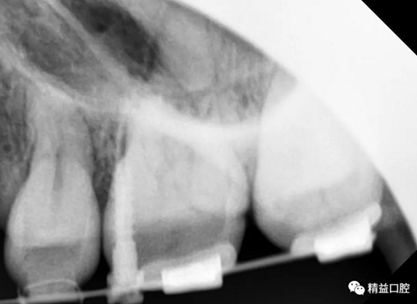

初次看到俊的牙片,我也驚訝到了,畢竟才27歲,上下門牙牙根吸收得非常嚴(yán)重,如果矯正,其中的風(fēng)險還是非常大的。

矯正前全口曲斷片

從片子上可以清除看到,上牙門牙牙根吸收非常厲害。